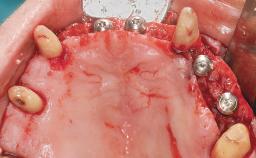

A 63-year-old male patient was referred for a consultation and treatment of partial edentulism in the maxilla. The patient presented with residual anterior teeth and declined a partial removable prosthesis. He reported that the maxillary posterior teeth had been extracted due to mobility and periodontal disease two months before the consultation. The patient’s chief complaint was that his residual maxillary teeth were mobile and that he was unable to chew. The patient’s desire was a stable and comfortable fixed maxillary rehabilitation. The patient was a light smoker (fewer than 10 cigarettes/ day), and his medical history was without significant findings. He was not on any regular medication at the time of consultation. The extraoral examination revealed a normal physiognomy with a correct distribution of the facial thirds. The patient presented a low lip line, and the transition line between teeth and soft tissues was not exposed during a forced smile.

# of Implants 6

Bone Augmentation Horizontal|Simultaneous